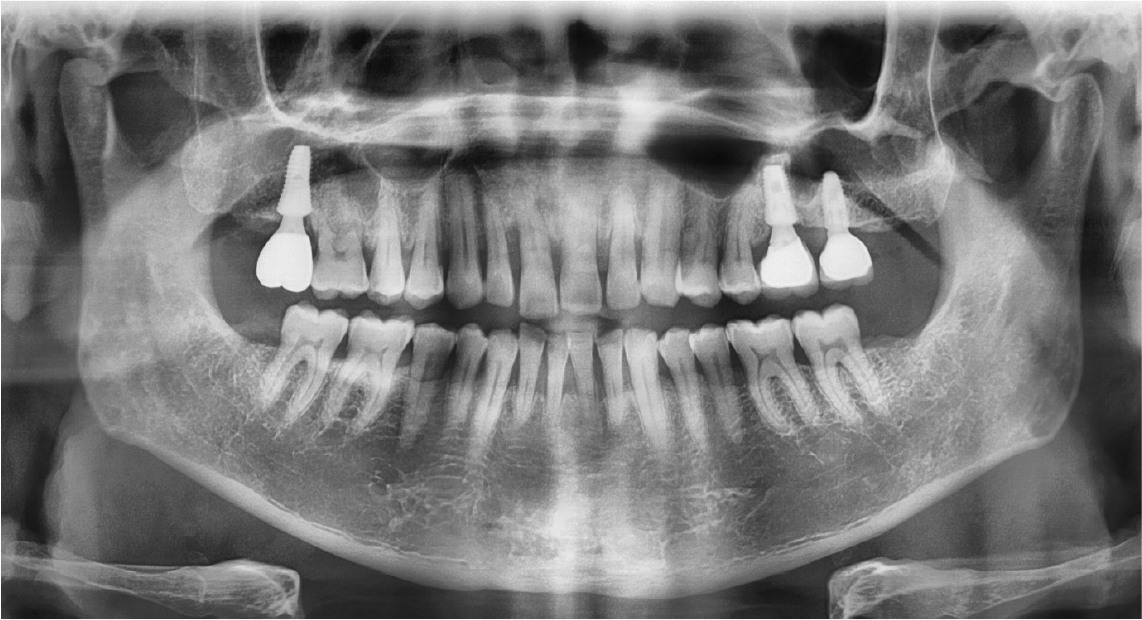

After the stuffy nose on the right side was completely gone, the bony window was extended anteriorly and the sinus membrane around perforated area was lifted. The perforated membrane was sutured (Rexlon nylon 4-0®; SM eng, Seoul, Korea) and the collagen wound dressing was inserted for the complete sealing (Fig. 5). Alloplastic bone-grafting material (A-oss®; Osstem implant Co., Seoul, Korea) was packed and the implant placement (Superline®; Dentium implant Co., Seoul, Korea) was performed immediately (Fig. 6). After operation, conservative treatment (augmentin 625 mg, acidified pseudo ephedrine HCL 2.5 mg, acetaminophen 500 mg, 3 times daily) continued for 1 week. After one week, the suture was removed and the discomfort symptom was disappeared. After 3 months later, occlusal loading started (Fig. 7). In the 3-months follow-up, the implant and lifted sinus bone formation were stable (Fig. 8). In the 2-years follow-up, the implant was left stable and the sinus lifted bone was maintained well (about 6 mm height) (Fig. 9).

In this study, the author performed simultaneous implantation, although there was perforation. The repair technique may be vary depending on the size of the membrane perforation. If a membrane perforation is <2 mm in diameter, it is not typically cause for concern and will not usually require any special treatment.16 If the perforation is larger, it needs to be closed and covered to prevent loss of the graft and secondary complication such as sinusitis.17 In large perforation, the collagen membrane that covered the perforation could not be supported by surrounding intact sinus membrane. Therefore it is impossible to maintain the position of the collagen membrane. Large membrane perforations often require complex repairs.18,19 Various methods can be used for the treatment of membrane perforation. In case of small perforation (<5 mm), the perforated membrane can be managed by using tissue fibrin glue, suturing or by covering it with a restorable barrier membrane. In case of large perforation (>5 mm), larger barrier membranes, lamellar bone plates or suturing either alone or in combination with fibrin glue can be used.12 In this case, the perforated membrane was repaired with suture and collagen wound dressing. Many authors did not recommend membrane suturing technique because of the extremely delicate features of the membrane. Also, the suture of the membrane can be enlarge the existing perforation or create a new one.18 And as in this case, the window can be opened wider and the membrane should be lifted wider in the process of approaching and preparing for suture. But if the approach is possible and the membrane is not too thin, suturing technique is an easy way to recover the membrane perforation. In this case, the size of the perforation was about 5mm in the first operation. The membrane was repaired with collagen wound dressing. However, infection occurred in the perforated area. In order to shorten the treatment period and for the management of the patient, the infection source and implant were removed, and at the same time, the sinus membrane repair using suture (Rexlon nylon 4-0®; SM eng, Seoul, Korea) was performed.20 The suturing membrane was used successfully for the closure of the perforation and dental implant was placed simultaneously. There were no serious infections. And clinical and radiographic findings at the 2-year follow up were adequate (Fig. 9).